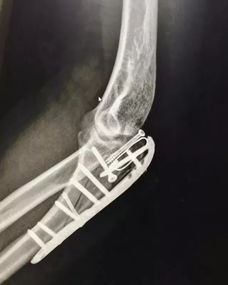

粉碎性骨折:多由直接暴力所致,骨折片碎成三塊以上者,稱粉碎骨折,多見于成年人,,

《什么是粉碎性骨折》(.unjs)。骨折線呈"T"形或"Y"形時,又稱"T"形或"Y"形骨折。